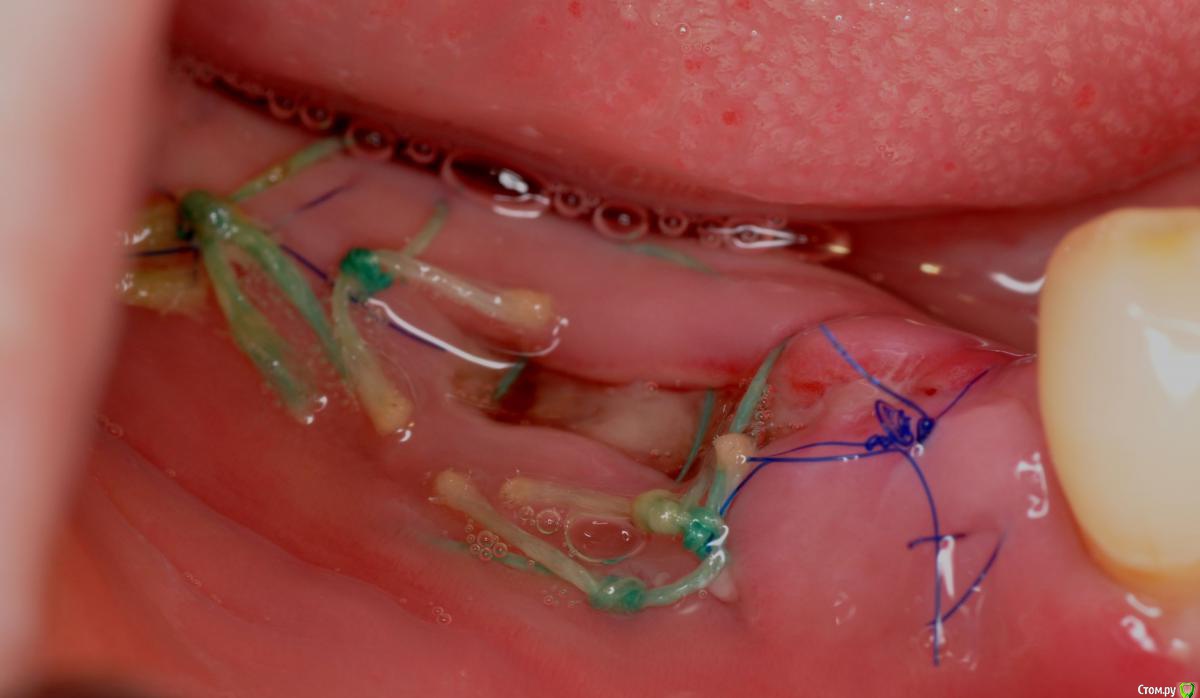

kriokov Опубликовано 23 ноября, 2015 Поделиться Опубликовано 23 ноября, 2015 а через пол года я этим Фторэксом ботинок себе заштопал на работе!) добраться до дома должно хватитьфторэкс в сравнении с унифлекс сразу в день вмешательствачерез 2 сутокчерез 8 суток фторэкс надулся и весь в дерьмецеснял фторэкс, дырки после него на раневой здоровыеснял все, слизистая как после дратвы где был фторэкс Ссылка на комментарий